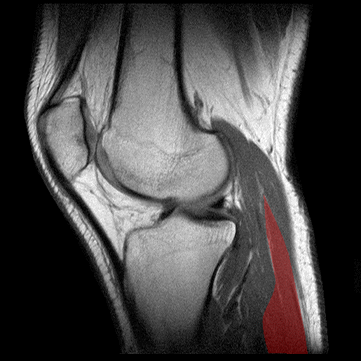

MUSCULO GEMELO

Definici�n: los m�sculos gemelos, formados por las cabezas medial y lateral se extienden en la parte syperficial del compartimento posterior de la pantorilla

Origen: Las cabezas medial y latreral del m�sculo gemelo salen de los c�ndilos medial y lateral del f�mur, respectivamente. Las dos cabezas se unen en la parte superior de la pantorilla.

Inserci�n: El m�sculo forma un tend�n ancho y plano a nivel de la pantorrilla media. El tend�n soleo se insera en la parte anterior del tend�n del gemelo para formar el tend�n de Aquiles que, a su vez, se inserta en la parte posterior del calc�neo posterior

Inervaci�n: El m�sculo gemelo est� inervado por el nervio tibial (S1, S2). El aporte sangu�neo est� asegurado por la arterial posterior tibial artery.

Funci�n: El m�sculo gemelo flexiona la pierna, extiende el pie (flexi�n plantar) y es supinador y abductor del mismo.